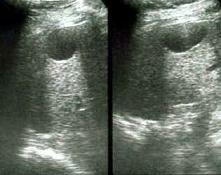

En los niños, esta tendencia alcista es preocupante y está asociada claramente al aumento de la obesidad infantil. Se realizó un estudio en Granada con 119 niños obesos y se demostró gracias a una ecografía hepática que el 43% de ellos presentaban esteatosis (hígado graso) y un 7,6% tenían un aumento de transaminasas (enzimas que se localizan en el hígado y que permiten transformar determinadas sustancias). Hay que recordar que el hígado es la mayor fábrica de nuestro cuerpo y casi siempre se altera por los malos hábitos alimentarios e inadecuados.